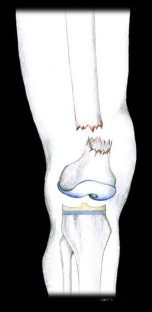

Abb. 2